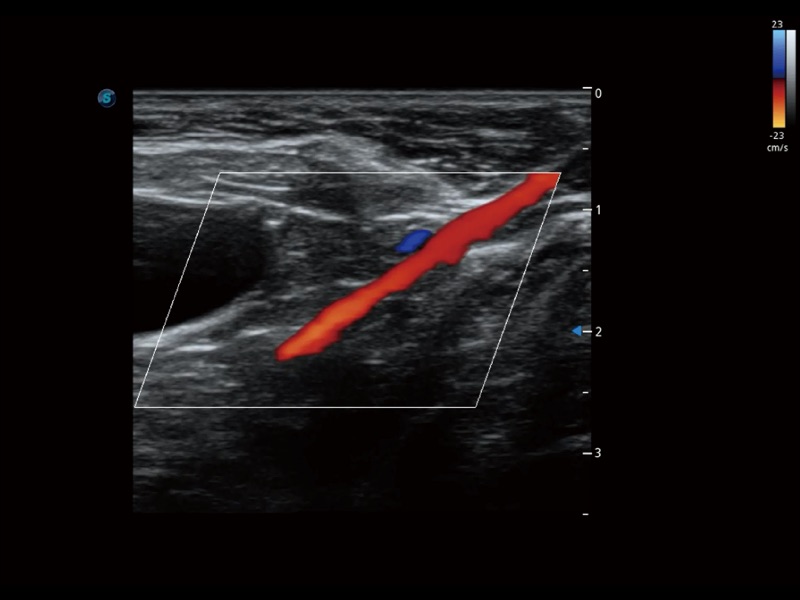

增强穿刺针在动物解剖结构中的位置,提高穿刺介入的安全性和准确性。

通过创新的 Matrix E自适应滤波器和超长时间域算法,极大提升超低速微细血流的检出能力,同时更精准地滤除软组织和噪声信号,为兽用医生提供以往无法通过常规血流获得的疾病诊断信息。

通过色彩血流和实时宽景相结合,可观察到完整的静脉或动脉的血流,方便医生检查。实时扫查过程中,如有任何操作失误也可以很容易地进行回扫擦除,而不会中断扫查。